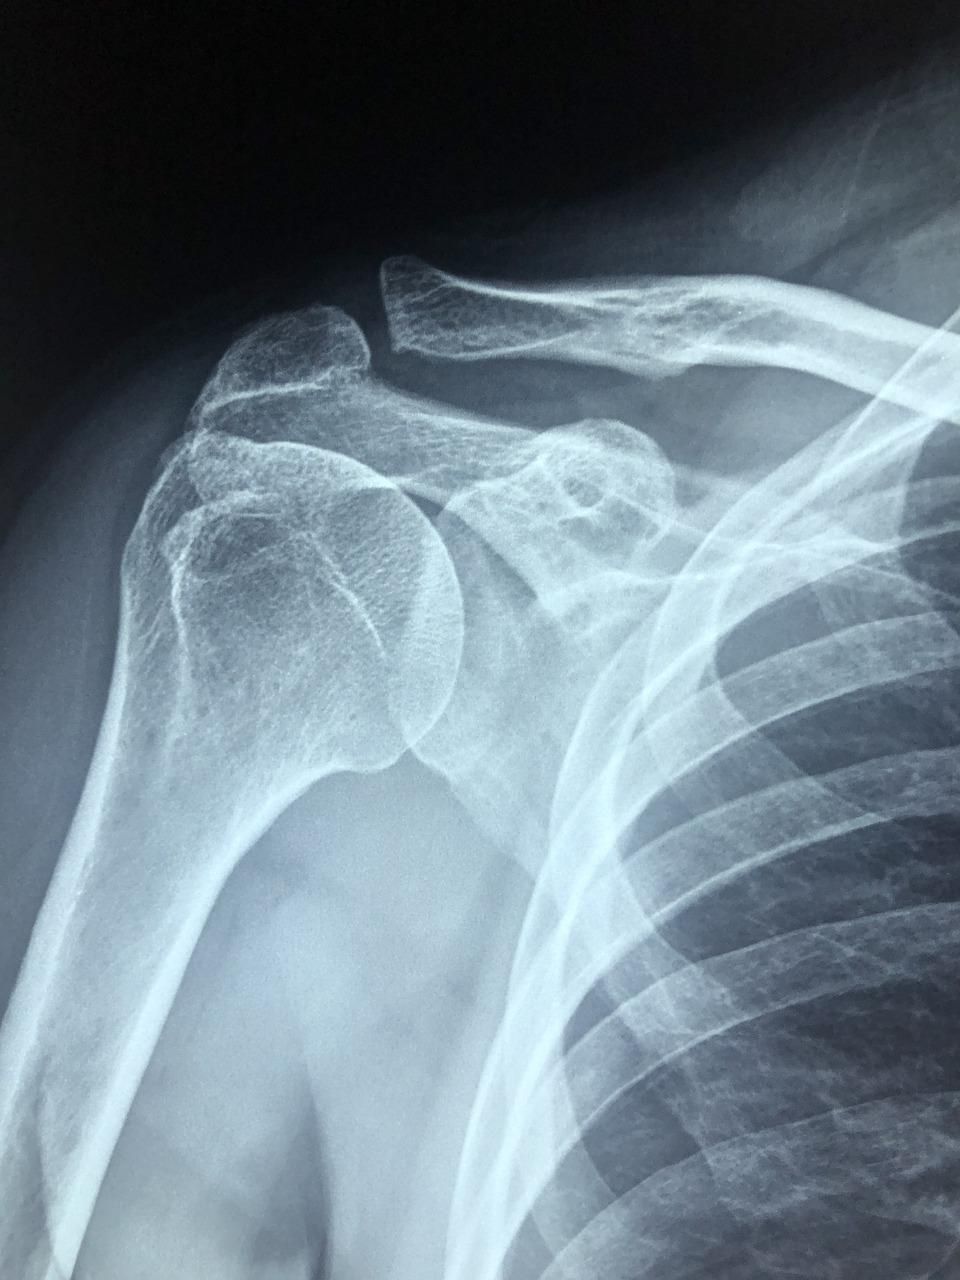

Dolor de hombro en Madrid centro tratado por un experto

El Dr. López Velázquez es un médico especialista en rehabilitación con amplia experiencia en el tratamiento eficaz del dolor de hombro.

- Artrosis.

- Esguince acromioclavicular.

- Dolor tras fractura.